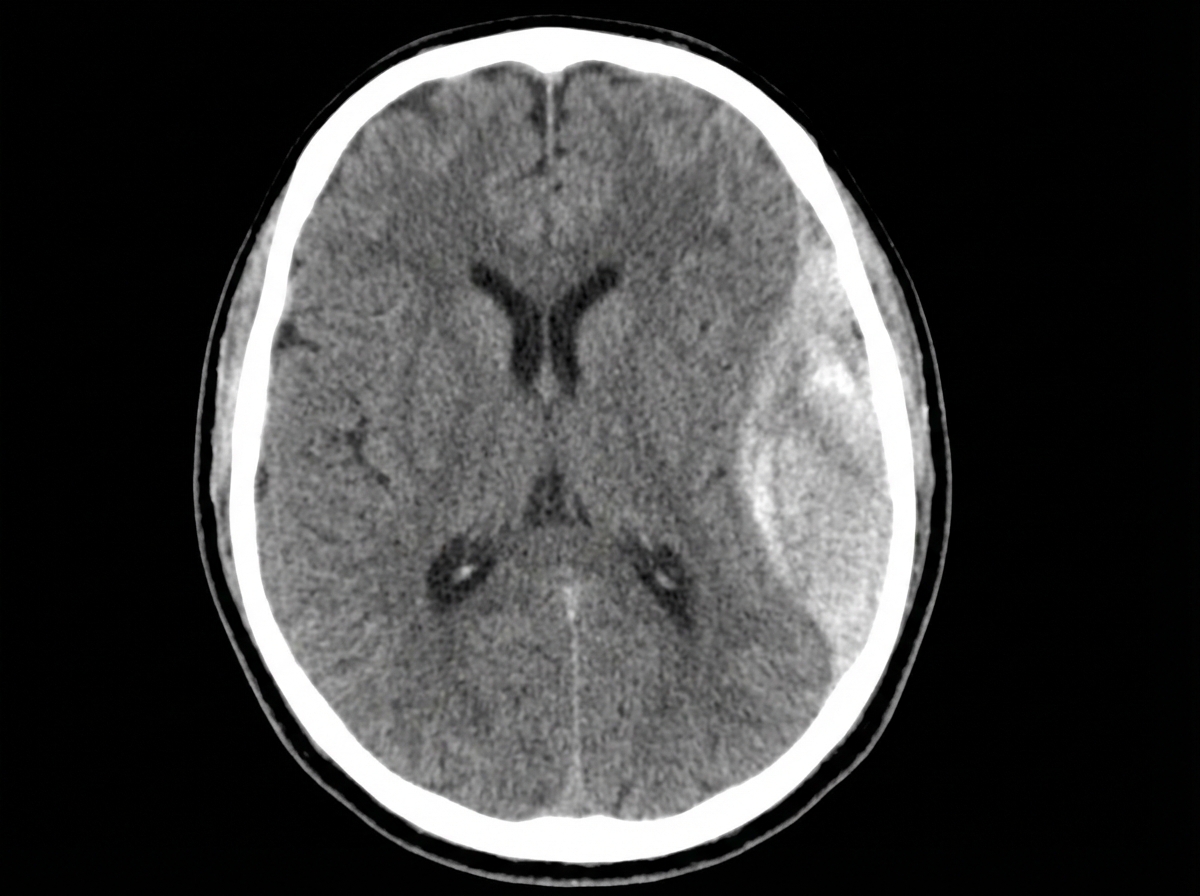

A 28-year-old man is brought to the emergency department by ambulance after developing an altered mental state following blunt trauma to the head. The patient was competing at a local mixed martial arts competition when he was struck in the head and lost consciousness. A few minutes later, upon regaining consciousness, he had a progressive decline in mental status. Past medical history is noncontributory. Upon arrival at the hospital, the temperature is 37.0°C (98.6°F), the blood pressure is 145/89 mm Hg, the pulse is 66/min, the respiratory rate is 14/min, and the oxygen saturation is 99% on room air. He is alert now. A noncontrast CT scan is performed, and the result is provided in the image. Which of the following structures is most likely affected in this patient?